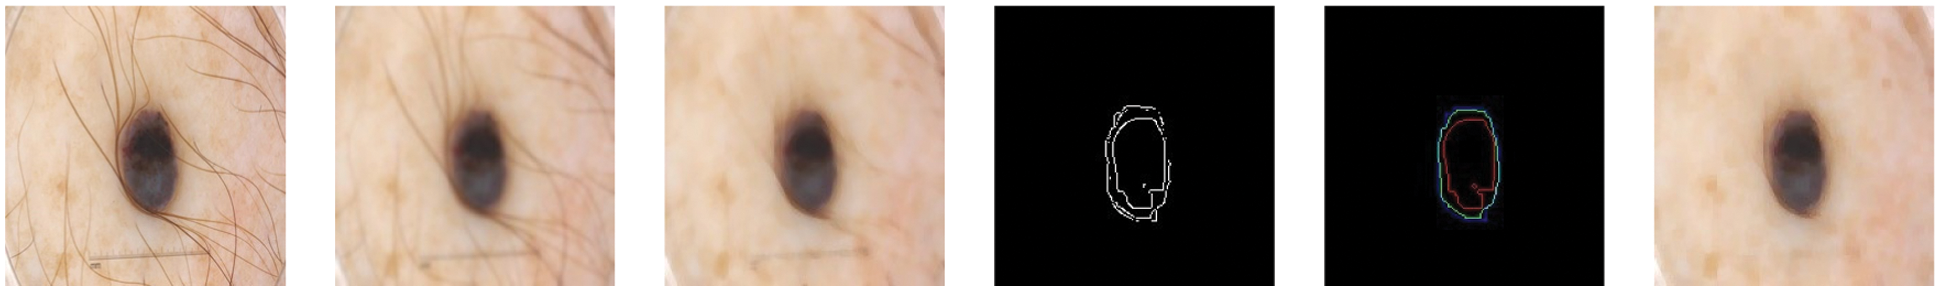

For filtering, we have used the input image as shown in Fig. 4 and applied Gaussian and median filtering with a 7 × 7 kernel. Median filters and different combinations of morphological operations can help to remove all possible from the skin image. We apply black-hat and closing morphological operations on the hairy images. After morphological operations, we prepare and intensify the hair contour to apply inpaint methods to remove the hairs from the skin lesion images. Fig. 4 presents the removal of all possible hairs from the skin lesion images.

Figure 4: For filtering, we have used the hairy image (1st image) and Gaussian (2nd image) and Median filtering (3rd image) with 7 × 7 kernel. Median filters remove all possible hairs from the skin lesion images and give plausible results. After filtering, different morphological approaches applied with Canny (4th image) and Laplacian (5th image) operations and performed to find proper shape of a lesion (6th image)

After filtering, we used several edge detection algorithms (Canny and Laplacian). The Laplacian algorithm gave us positive results as compared to others (Canny). After edge detection (IMed(x,y)), we multiply the edge detected image with image that contains shape of lesion (IMLes(x,y)) using Eq. (4). It deletes the unwanted information (unwanted parts of skin lesions).